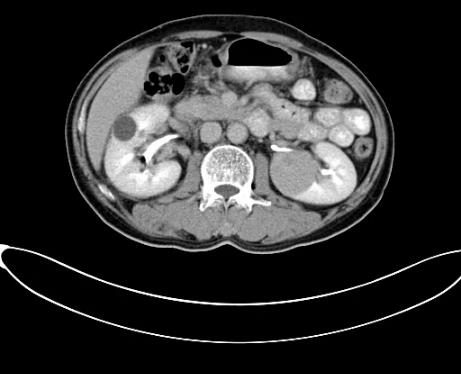

据安图叔叔的儿子回忆道,安图叔叔在体检前没有发现任何不适的症状,在体检后才知双肾占位,右肾下级占位16.1*7.2cm,左肾下级肿瘤约3.7*4.3cm的情况。突如其来的病情让一家人陷入了恐慌,从未想过一个健康自律的人会突然间就被检出肾癌,还是双肾。安图叔叔的儿子激动地说道:“我当时一下子懵了,父亲之前表现那么健康,一查竟病得很重,为确诊我把父亲转接到新加坡就诊,那边的医生在看了我父亲的片子后都表示这是肿瘤,要做切除双肾然后再透析,对于我们来说,切肾这样的治疗方案对我们来说是无法接受的,父亲毕竟一把年纪,这样做法太伤他身体。”

2017年9月29日,从CT影像看到右肾情况更为严重。为减缓肿瘤增长的速度,专家进行商议后,最终决定由牛立志教授主刀为安图叔叔进行了右肾肿瘤冷冻消融术。手术开始后,牛立志教授在CT和超声引导下,同时使用两根冷冻针固定病灶,精准灭活肿瘤;术后很成功无不良反应。术后一周进行第二次双肾肿瘤冷冻消融术。安图叔叔儿子笑道:“当时真的很紧张,医生劝慰我无须担心,都交给他们,我们都很清楚知道父亲的病情,真的很感谢也很庆幸我父亲遇到复大的医护人员,免受开刀之痛。住院期间医护人员很尽心尽力的照顾父亲,手术的成功离不开他们的辛劳付出。”